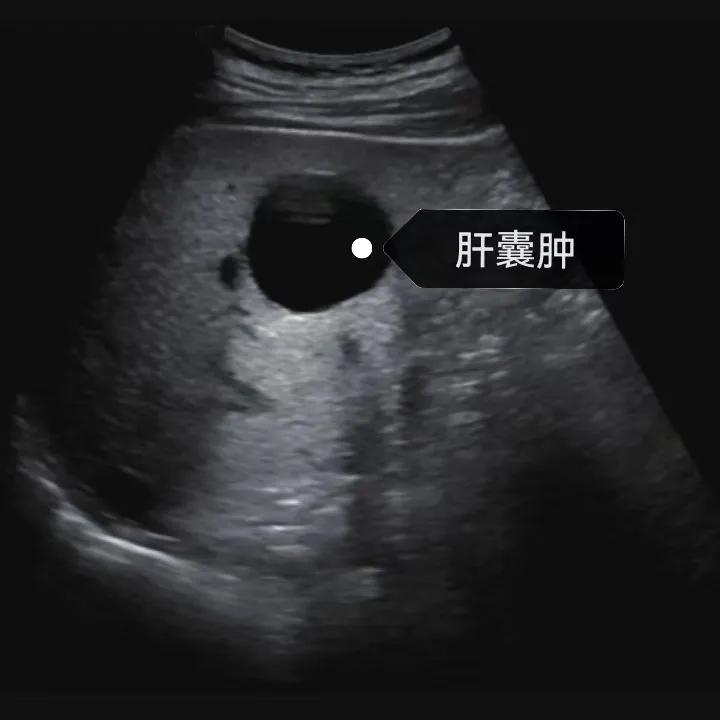

超聲通常是診斷肝囊腫的首選方法,彩超對肝囊腫的檢出率可達(dá)98%,<1cm的囊腫也可檢出。肝囊腫常表現(xiàn)為圓形或橢圓形無回聲,包膜光滑完整,邊界清晰,可有側(cè)壁回聲失落征象,后方回聲增強(qiáng)。病程長、囊腫較大者或囊內(nèi)有過出血、感染者,無回聲腔內(nèi)可見少量絮狀回聲漂浮。超聲對肝囊腫的診斷準(zhǔn)確而靈敏,且方法簡單、無創(chuàng)、費(fèi)用低、可重復(fù)性高,因此常常被作為首選。